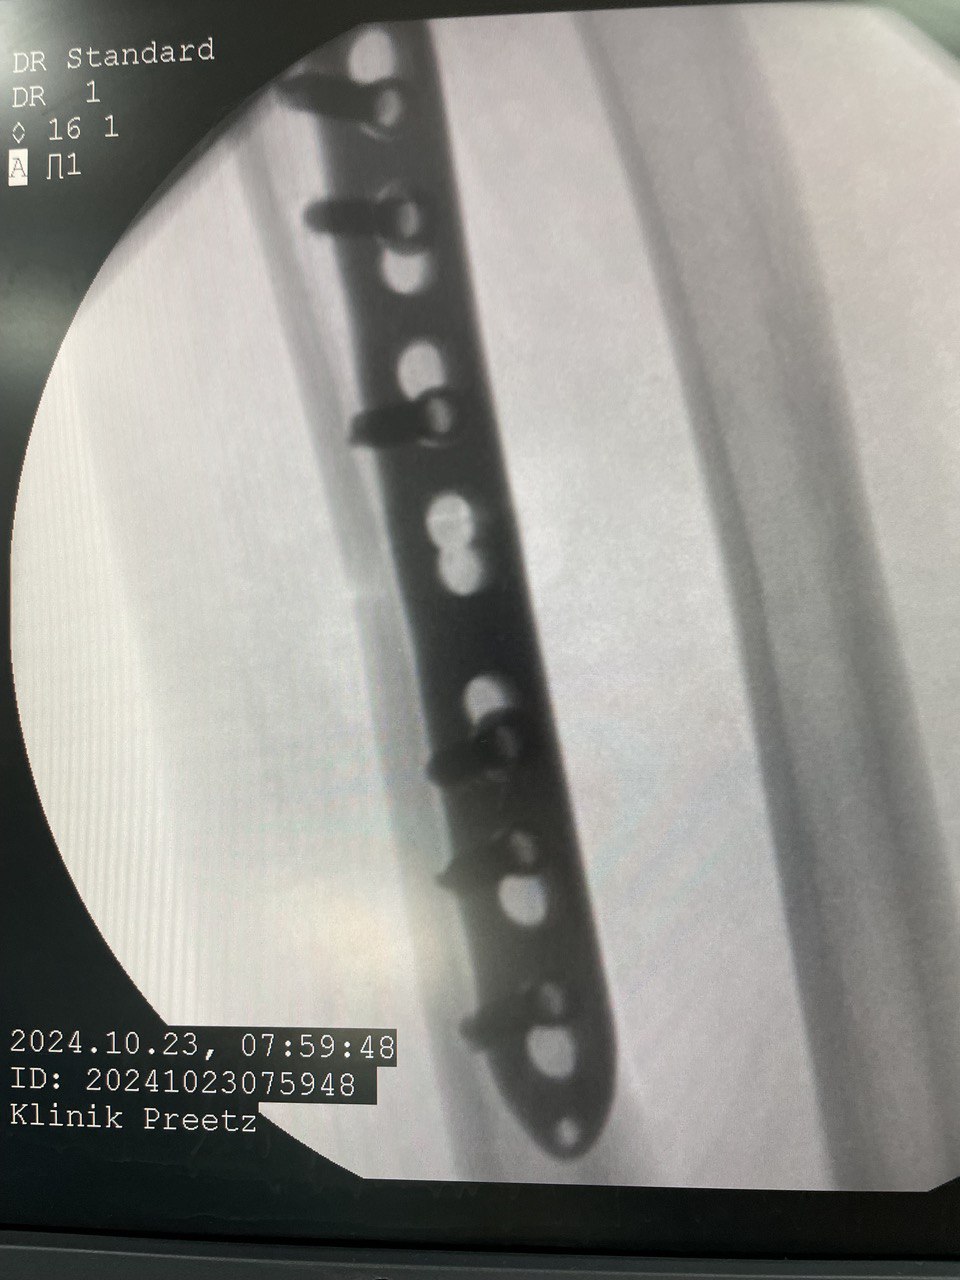

Клинический случай: внутрисуставной перелом дистального метаэпифиза лучевой кости — операция (остеосинтез пластиной)

Этап остеосинтеза: доступ, фиксация и контроль положения пластины.